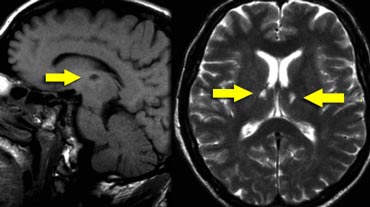

Koedam score for Parietal Atrophy

In addition to medial temporal lobe atrophy, parietal atrophy also has a positive predictive value in the diagnosis of AD.

Atrophy of the precuneus is particularly characteristic of AD (15).

This is particularly the case in young patients with AD (presenile AD), who may have normal MTA-scores.

The Koedam scale rates parietal atrophy - assessed in sagittal, coronal and axial planes.

In these planes, widening of the posterior cingulate and parieto-occipital sulci as well as parietal atrophy (including the precuneus) is rated (Table).

Koedam scale grade 0-1 Koedam scale grade 0-1

Koedam scale grade 0-1

Sagittal T1-, axial FLAIR- and coronal T1-weighted images illustrating the Koedam scale of posterior atrophy.

When different scores are obtained in different orientations, the highest score must be considered (16).

Koedam scale grade 2-3 Koedam scale grade 2-3

Koedam scale grade 2-3

The yellow arrows point to extreme widening of the posterior cingulate en parieto-occipital sulci in a patient with grade 3 posterior atrophy.